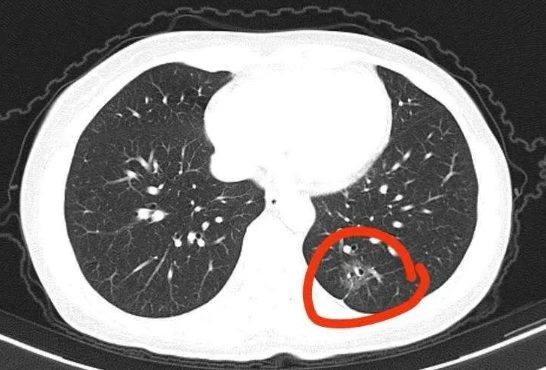

此前,汪建民接受采访时表示,因背后剧痛,检查发现肺部出现恶性肿瘤,癌细胞扩散并吞噬颈椎最后一节和脊椎第一节相连处,且脑部也出现两颗肿瘤。公开资料显示,汪建民1968年1月23日出生于中国台湾,花名“铁头”,知名男演员、主持人。多次助理主持知名综艺节目《康熙来了》,代表作品有《台湾灵异事件》《波丽士大人》《拥抱大白熊》等。刘谦透露自己三四年前就发现了肺结节,后来发生了病变,那什么样的结节更危险呢?浙江省杭州市第一医院心胸外科副主任医师冯兴2023年在其医院公众号刊文中提醒,一般来说,初次CT检查发现的肺部结节80%-90%都是良性病变。但如果身上出现以下两种肺结节,最好要足够重视,定期随诊,必要时手术切除。1.看结节的大小和形态,如果结节大小8毫米以上,结节边界不清的,分叶状,边缘毛刺,结节内有空泡及血管穿行等特点,需要定期复查。复查中结节有增大或实性成分增多,最好通过相关诊治手段协助明确或者手术切除,这类结节随着时间的推移,有可能变成肺癌。2.结节很小,但随着时间增长有不断增大的趋势,需警惕肿瘤风险,必要时需手术切除。